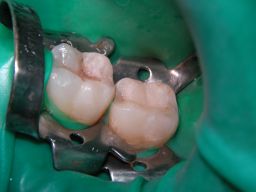

![]() | Am Ende waren es sogar 3, nicht nur 2 Füllungen (wer sieht die 3.?). Das grüne Latexgummi ist Kofferdam (=Spanngummi), der manchmal die Arbeit erleichtert, weil er den Speichel fernhält. Zuzahlung für die Kassenpatientin 2 * 30 . Mit Speichelfilm sind solche Füllungen im Alltag nicht mehr zu erkennen. |